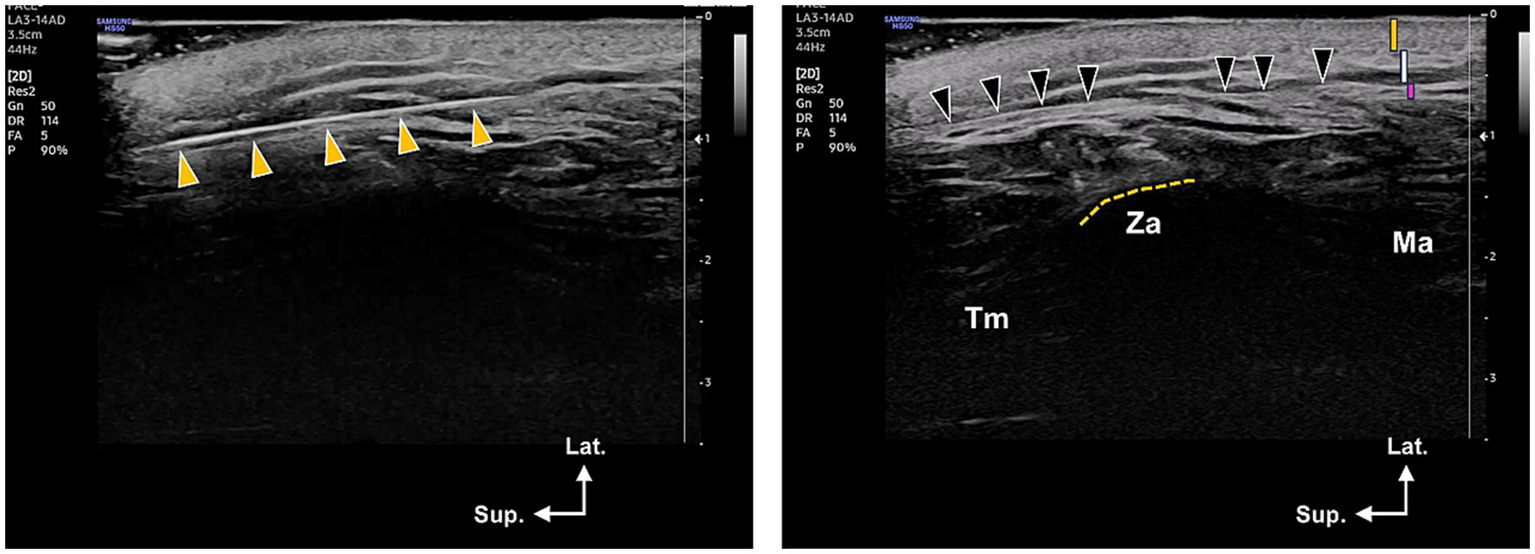

Figure 5

Ultrasonography images showing the location of the thread within the lateral face. The left image indicates the cannula’s location at the temple area, which was taken at the level of the lateral canthus. The yellow arrowheads point to the thread’s position within the temporoparietal or superficial temporal fascia. The right image displays the thread’s location within the subcutaneous layer (indicated by black arrowheads, which refer to the supra-SMAS in this article), specifically the deep portion of the subcutaneous layer just superficial to the SMAS layer. This image was taken at the zygomatic arch (ZA) level. In the upper right corner of the right image, the orange, white, and pink bars represent the skin, subcutaneous, and SMAS layers, respectively. Tm, Temporalis muscle; Ma, masseter muscle; Lat., lateral, Sup., superior.

Measurements were obtained from contrast-enhanced micro-CT datasets using digital calipers in VGStudio MAX (Volume Graphics, Heidelberg, Germany). Distances were measured at two representative points along the mid-portion of the thread trajectory, and mean values were calculated. The mean thread insertion depth from the skin surface was 6.8 ± 1.1 mm, while the mean distance between the thread path and the SMAS plane was 1.2 ± 0.4 mm. However, minimal movement was observed in the deeper portions of the thread’s trajectory. Despite being inserted into the subcutaneous layer, there were no cases where the thread appeared through the skin, such as causing dimpling. After thread insertion and investigation within the lateral facial tissue, dissection of the specimens revealed no damage to vessels, nerves, and muscular structures in the lateral face area.